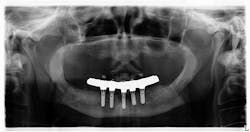

I typed in www.whatimplantisthat.com and was met with a page full of radiographic photos of implants—900-plus of them (figure 2). Wowza. I didn’t realize the full extent of the variety of implants out there. This, in and of itself, is fantastic. To begin your search, on the left side of the website, there is a list of filters that make the magic happen. What's even cooler is, if you can't figure it out on your own or are unsure of your diagnosis, you can pay to have someone help you.

Figure 2

Because I am naturally curious, I wondered about the genesis for this website. It has a tremendous wealth of information, and clearly a lot of thought and effort was put into it. Where did the idea come from, and can one really identify 900-plus implants just from a single radiograph? Apparently so. According to the website's creators, you just have to know what to look for. Details, baby, details!